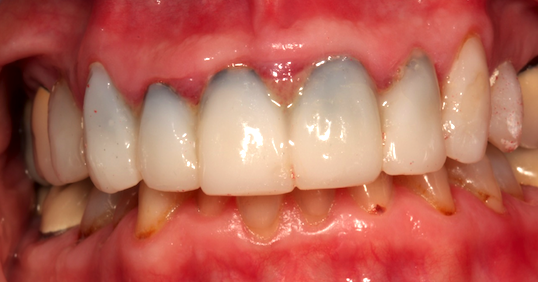

I received this image the other day with a question about what causes the black line under veneer provisionals. There are obviously tissue issues here as well and for our purposes here we will focus on the black line.

That line is actually an accumulation and proliferation of a bacteroides strain, an anaerobic bacteria that will stain dentin. It is a common contaminant in the mouth and will grow quickly under provisionals if they are not well sealed and if the tissue is not completely healthy prior to the preparation and provisionalization process.

Prevention is very easy. First, don’t prep teeth in the presence of unhealthy tissue! If the preps must be done in the presence of inflammation because of poor margins on existing restorations, then wait for the final impression until after the tissue is healthy.

Prior to luting the provisionals to the teeth, ensuring the excellence of the marginal integrity of the provisionals is critical to stopping, or at least minimizing, marginal leakage.

The second step prior to luting is to use either a chlorhexidine gluconate scrub such as Concepsis from Ultradent or a gluteraldehyde application such as Gluma from Heraeus. Both solutions are antibacterial and if applied according to the manufacturer’s directions will disinfect the surfaces of the preps and prevent the black line from forming.